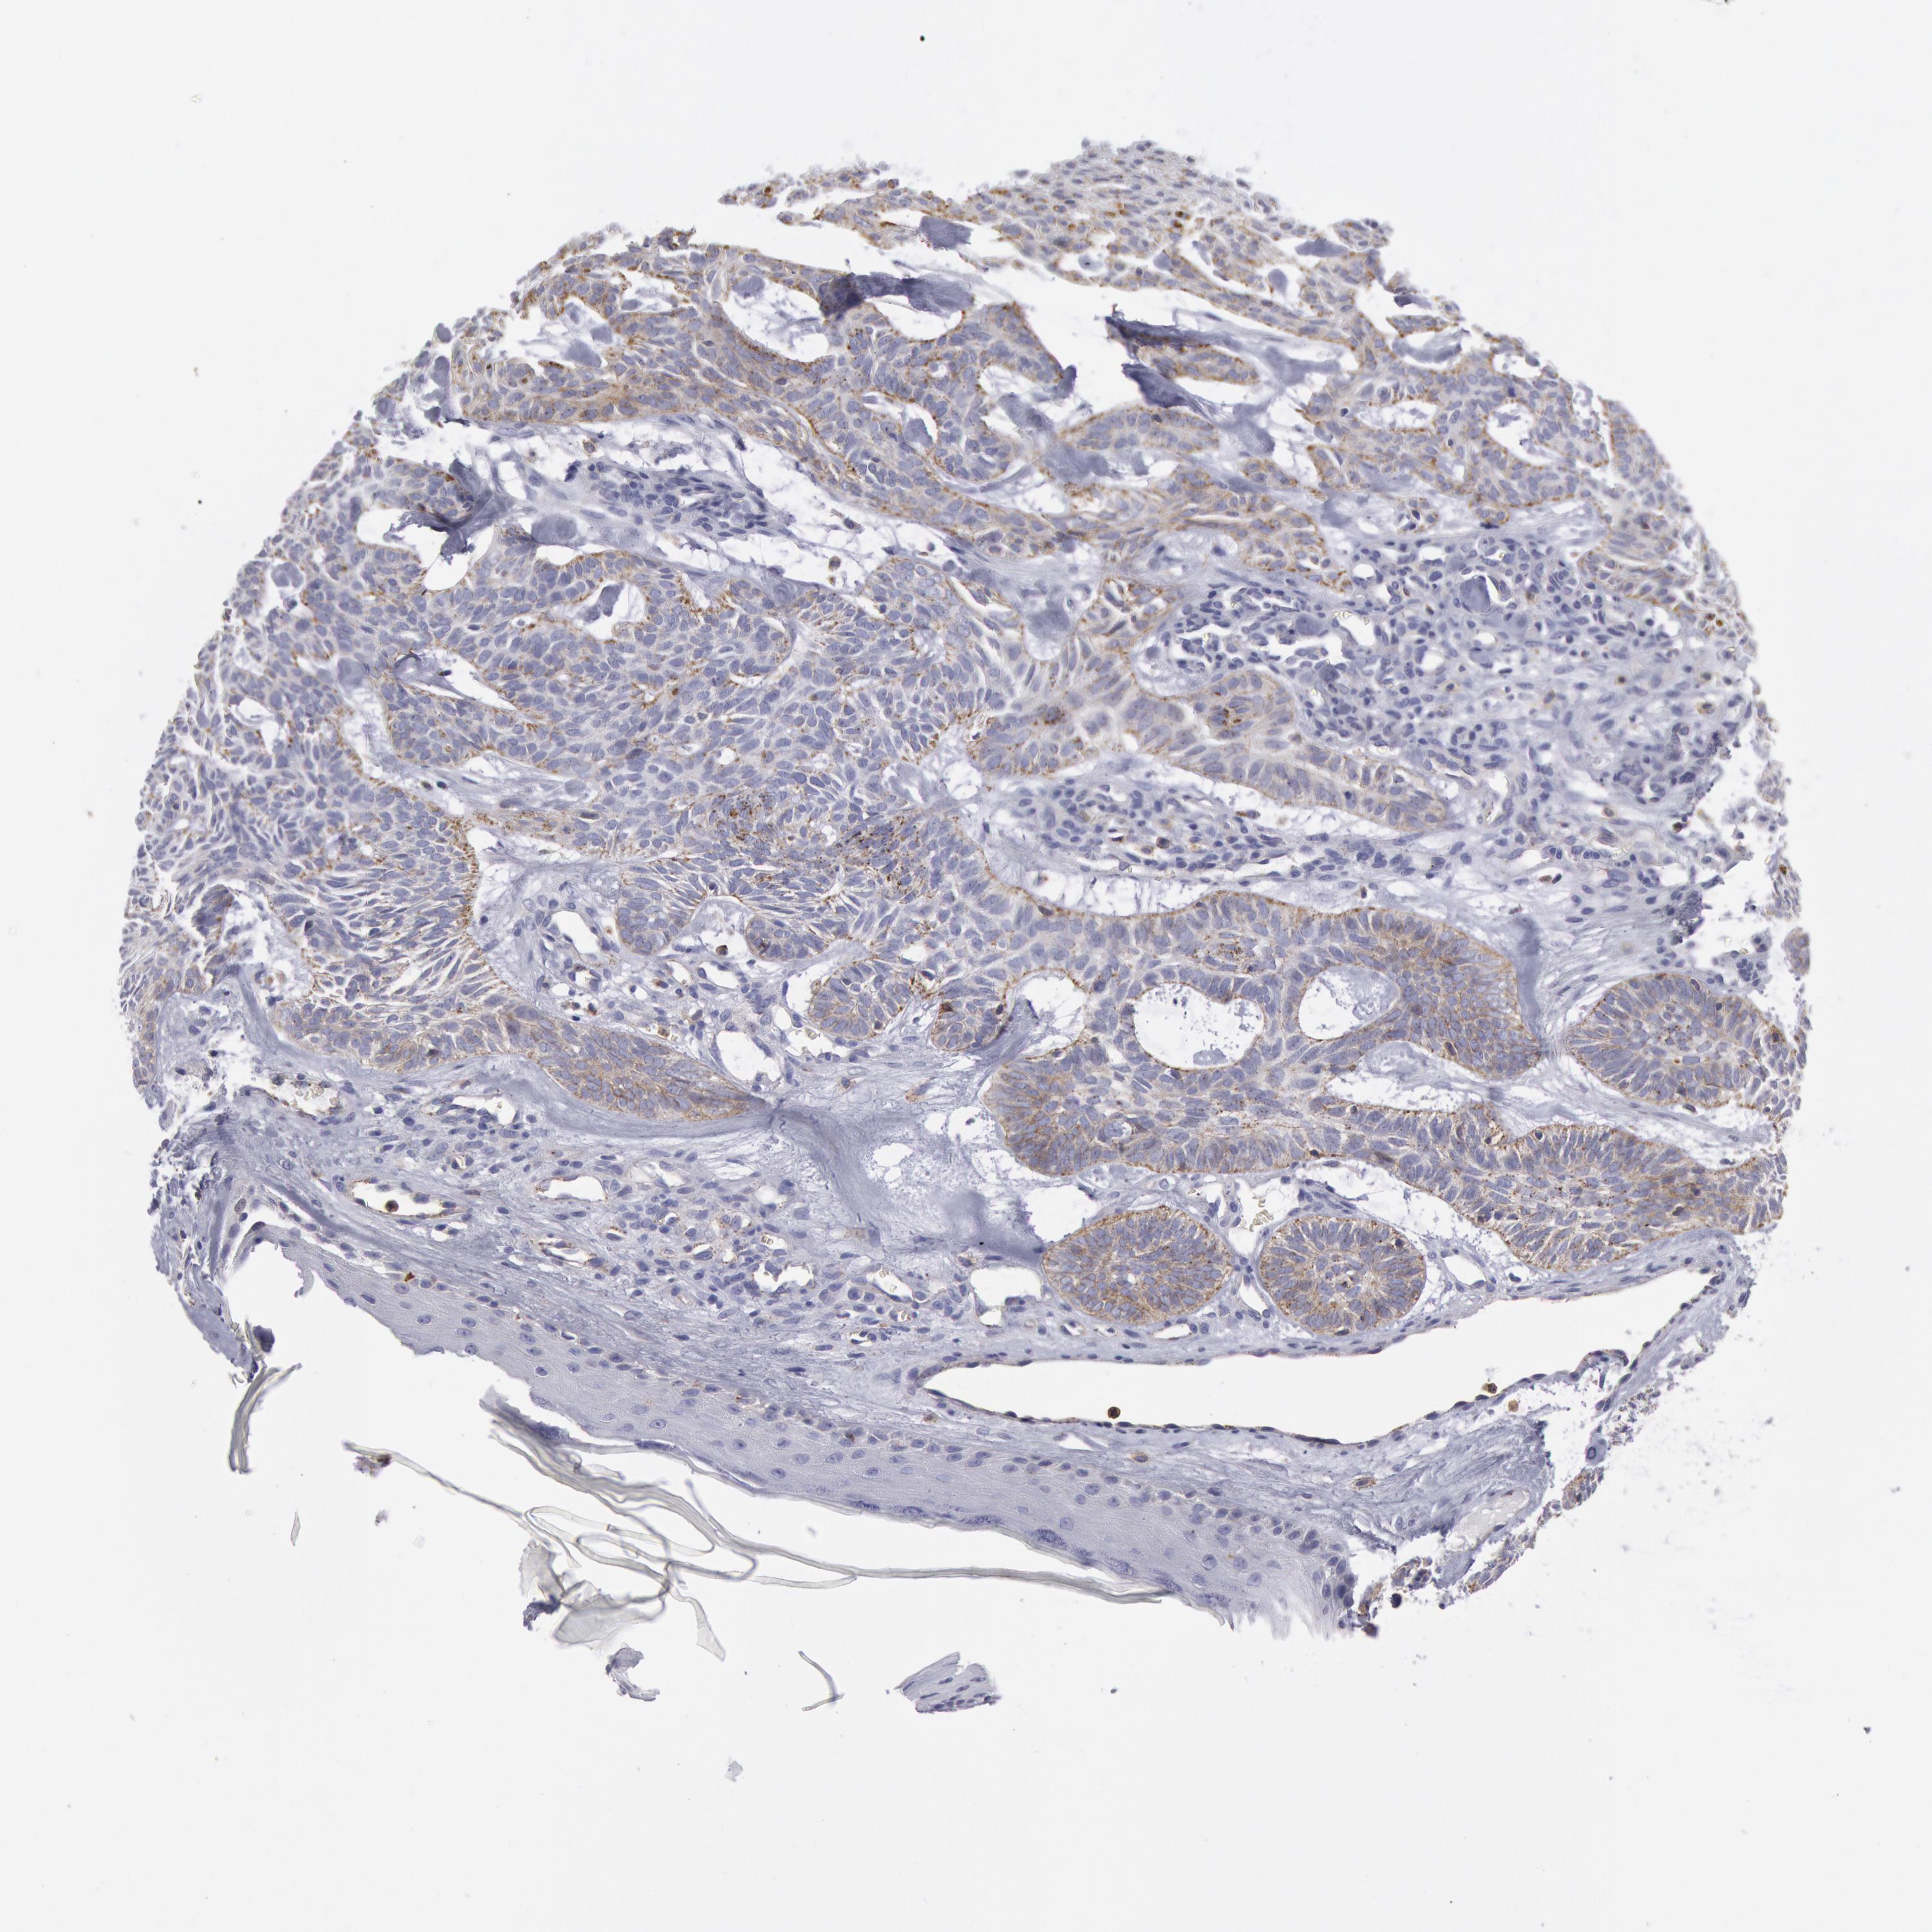

SKIN CANCER - Protein expressioni

A mouse-over function shows sample information and annotation data. Click on an image to view it in a full screen mode. Samples can be filtered based on level of antibody staining by selecting one or several of the following categories: high, medium, low and not detected. The assay and annotation is described here.

Each image is clickable and will lead to virtual microscopy that enables deeper exploration of all samples and also displays staining intensity scores, fraction scores and subcellular localization as well as patient and tissue information for each sample.

Antibody HPA001393

Staining

High

Medium

Low

Not detected

Intensity

Strong

Moderate

Weak

Negative

Quantity

>75%

75%-25%

<25%

None

Location

Nuclear

Cytoplasmic/membranous

Cytoplasmic/membranous,nuclear

Squamous cell carcinoma, NOS